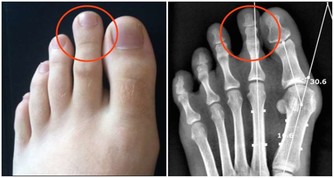

***5.潤滑關節。***蹲姿通過下肢有規律的折疊,對關節周圍組織是一種很好的伸展鍛煉,對膝關節和髖關節尤其適用。